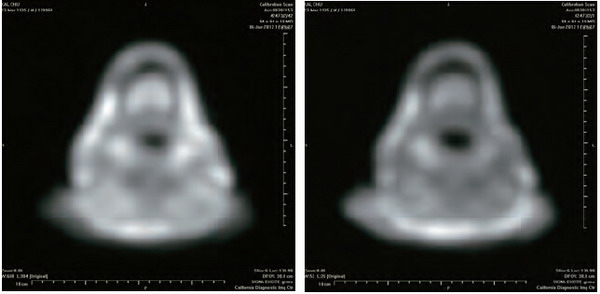

开初仁波且MRI核磁共振脑断层扫描医学图片

这是开初仁波且修金刚换体禅后,在加州医疗中心检查身体时拍摄的MRI核磁共振检测照片。可以清晰看见开顶后,头顶大乐轮门处头骨、皮肉等大开,开口宽约两英寸,脑髓开出鸡蛋大的凹洞。更令人震撼的是,当开初仁波且拍摄扫描照片时,整块头骨突然不见,而呈现出弥勒菩萨乳胎婴童像,身搭俱袍,手脚呈现,心空大洞,跏趺而坐,在电脑上清晰可见五官面容,眼睛、鼻子、嘴巴。